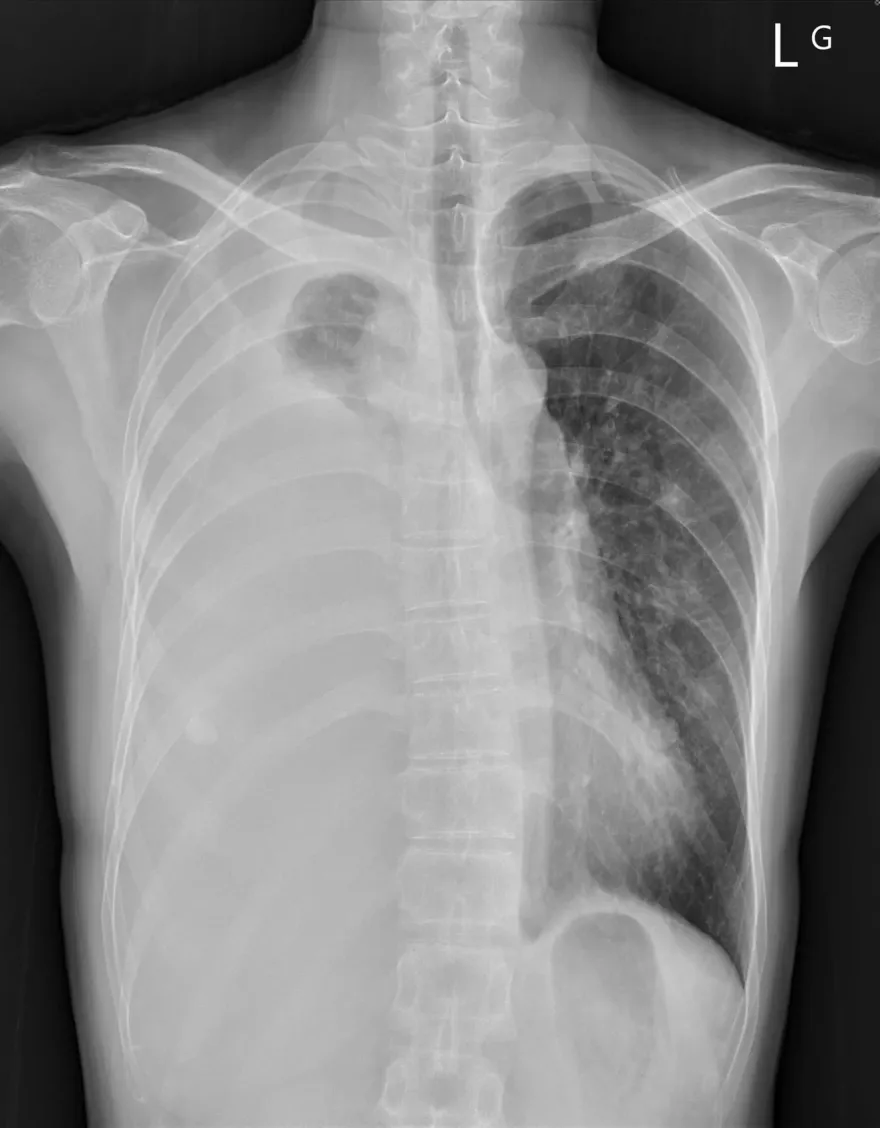

男童染「黴漿菌」高燒4天成肺炎!住院惡化且肋膜積水

肺部X光